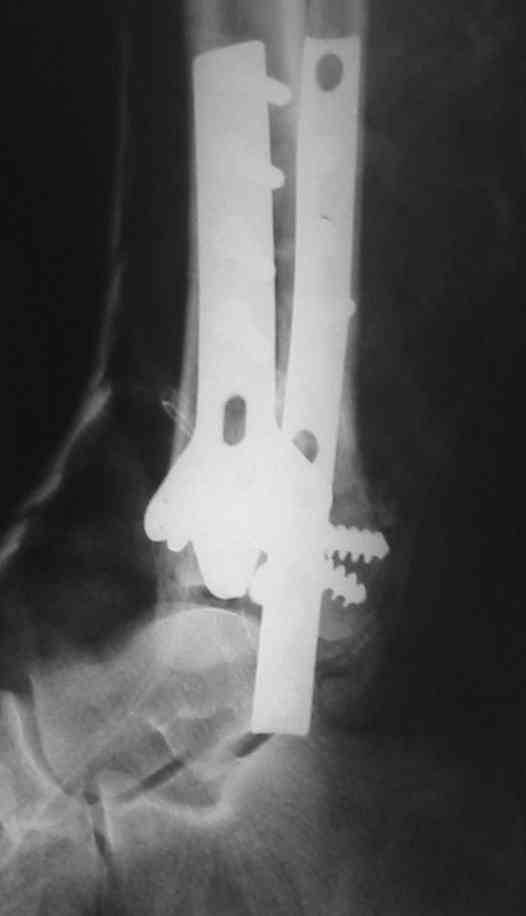

Мне кажется, что все конечно далеко от идеала. Сложный перелом. Есть ощущение, что малоберцовая кость (ключ!) фиксирована с ротацией и удлинением. Снимки конечно необходимо сделать в правильных проекциях и без гипса...

В голеностопном суставе обязательны 3 стандартные ренгенологические проекции: прямая, латеральная и мортиз. Без них невозможно трактовать состояние голеностопа.